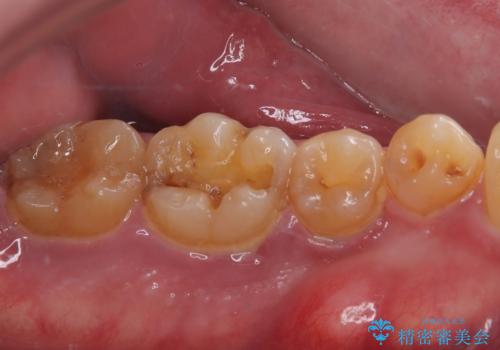

咬合力で破折した奥歯 抜歯即時埋入インプラントによる補綴治療

- 食事中に奥歯が痛むとのことで来院された患者様です。

レントゲンやCTより、深くまで破折していることが分かり、抜歯が必要な状態でした。

歯槽骨の状態は良好であったため、抜歯即時埋入インプラントによる補綴治療を行うこととしました。

インプラント埋入時に植立具合の安定性を測定したところ、十分な数値が得られたため、速やかに仮歯を装着して咬合回復をさせることができました。

抜歯を含めた外科処置を1回に抑えることができ、あっという間に治療を終えることができました。